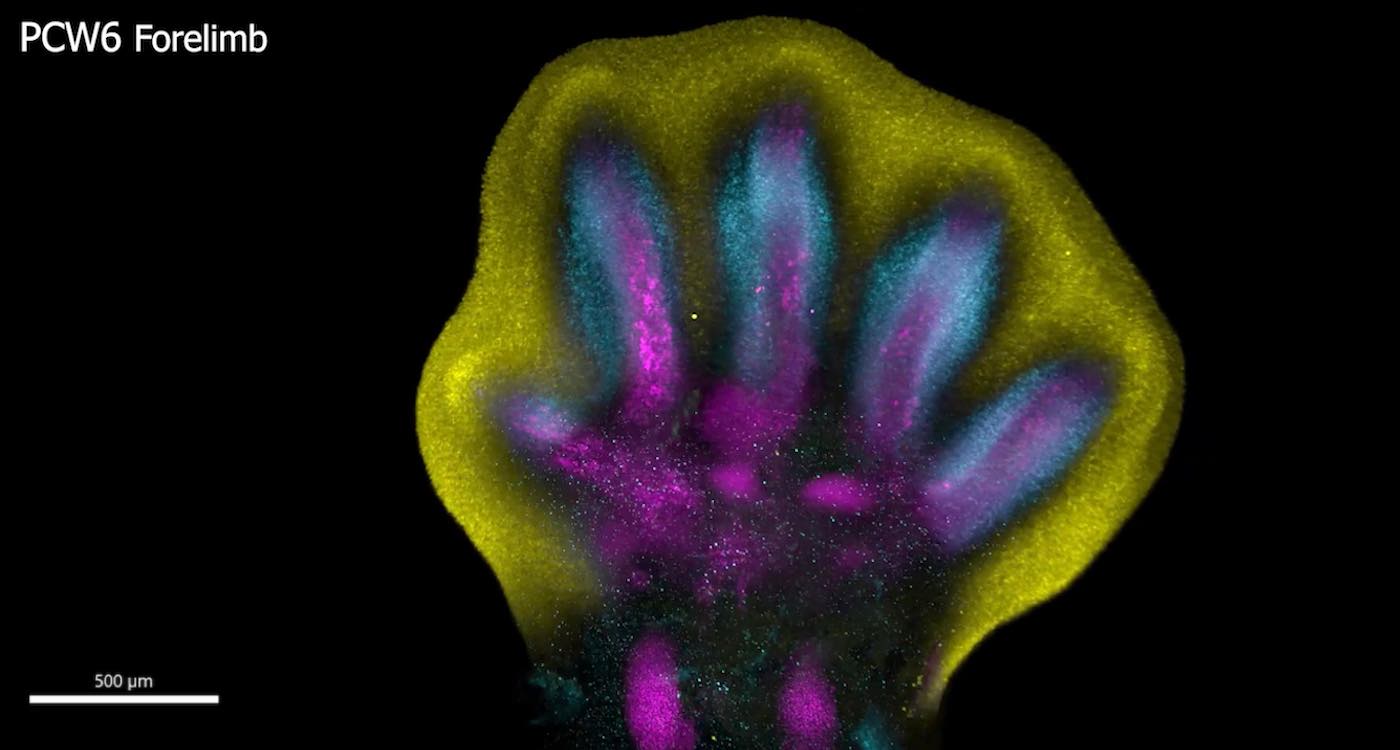

Special staining of the tissue revealed clearly how cell populations differentially arrange themselves into patterns of the forming digits.

Human fingers and toes do not grow outward; instead, they form from within a larger foundational bud, as intervening cells recede to reveal the digits beneath.

After around seven weeks of cell development, an “orchestrated cell death” finally unveils the well-defined shapes of fingers or toes.

Limbs are known to initially emerge as undifferentiated cell pouches on the sides of the body, without a specific shape or function. But after 8 weeks of development, they are well differentiated, anatomically complex and immediately recognizable as limbs, complete with fingers and toes.